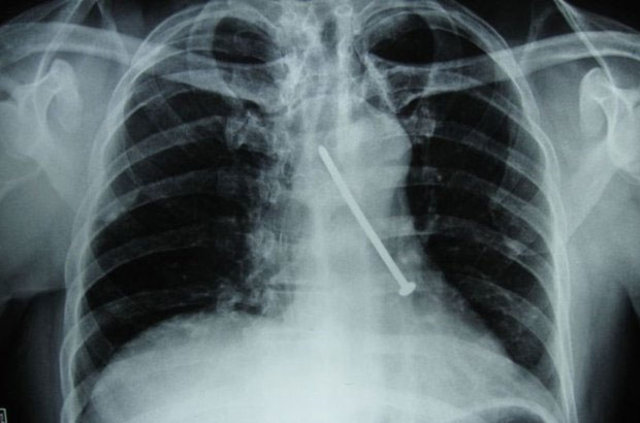

İzmir'deki Tepecik Eğitim ve Araştırma Hastanesi Çocuk Gastroenteroloji Bölümü'nün, yabancı cisim yutan çocukların nefes ve borusu ile midelerinden çıkarttığı, anahtarlık, madeni para, saat pili, ataç, çengelli iğne ve çivi gibi objeler görenleri şaşkına çevirdi.

Çocukların nefes ve borusu ile midelerinden çıkartılan, anahtarlık, madeni para, saat pili, ataç, çengelli iğne ve çivi gibi objeler görenleri şaşkına çevirdi. Anne ve babaların çok dikkatli olması gerektiğini söyleyen Doç. Dr. Maşallah Baran, şöyle dedi:

Genellikle yabancı cisimler 'X' ışınıyla görülebilir. Direk grafi ile metal ve 'X' ışınına duyarlı cisimleri rahatlıkla görebiliyoruz. Ama plastikleri göremiyoruz. Bu durumda oyuncağın bir parçasıyla yutulan parçayı anlamaya çalışıyoruz."